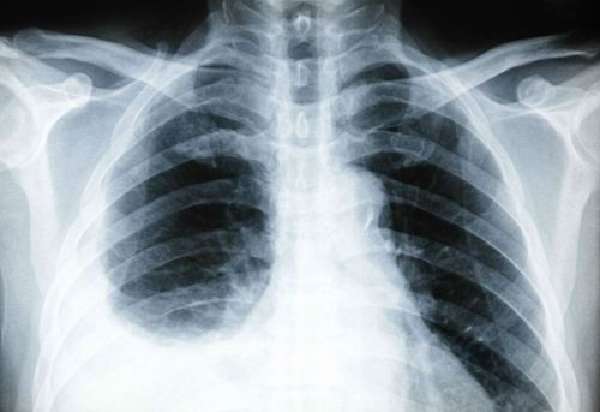

- рентген грудной клетки – показывает состояние позвоночника, костей, ребер;

обзорная рентгенография органов грудной полости — для диагностики заболевания легких и органов средостения, а также некоторых болезней сердца;